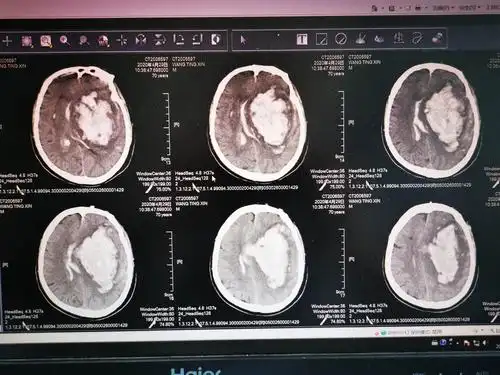

术前头颅ct,出血量约170ml

ct提示左侧基底节,丘脑,颞叶,枕叶广泛性脑出血.

多通道微创治疗大量脑出血一例